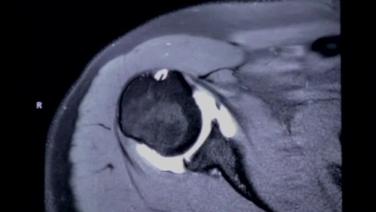

Surgeon's approach to Reading an MRI - Stephanie Muh, MD

MRI & X-ray Review Labral Tear Shoulder